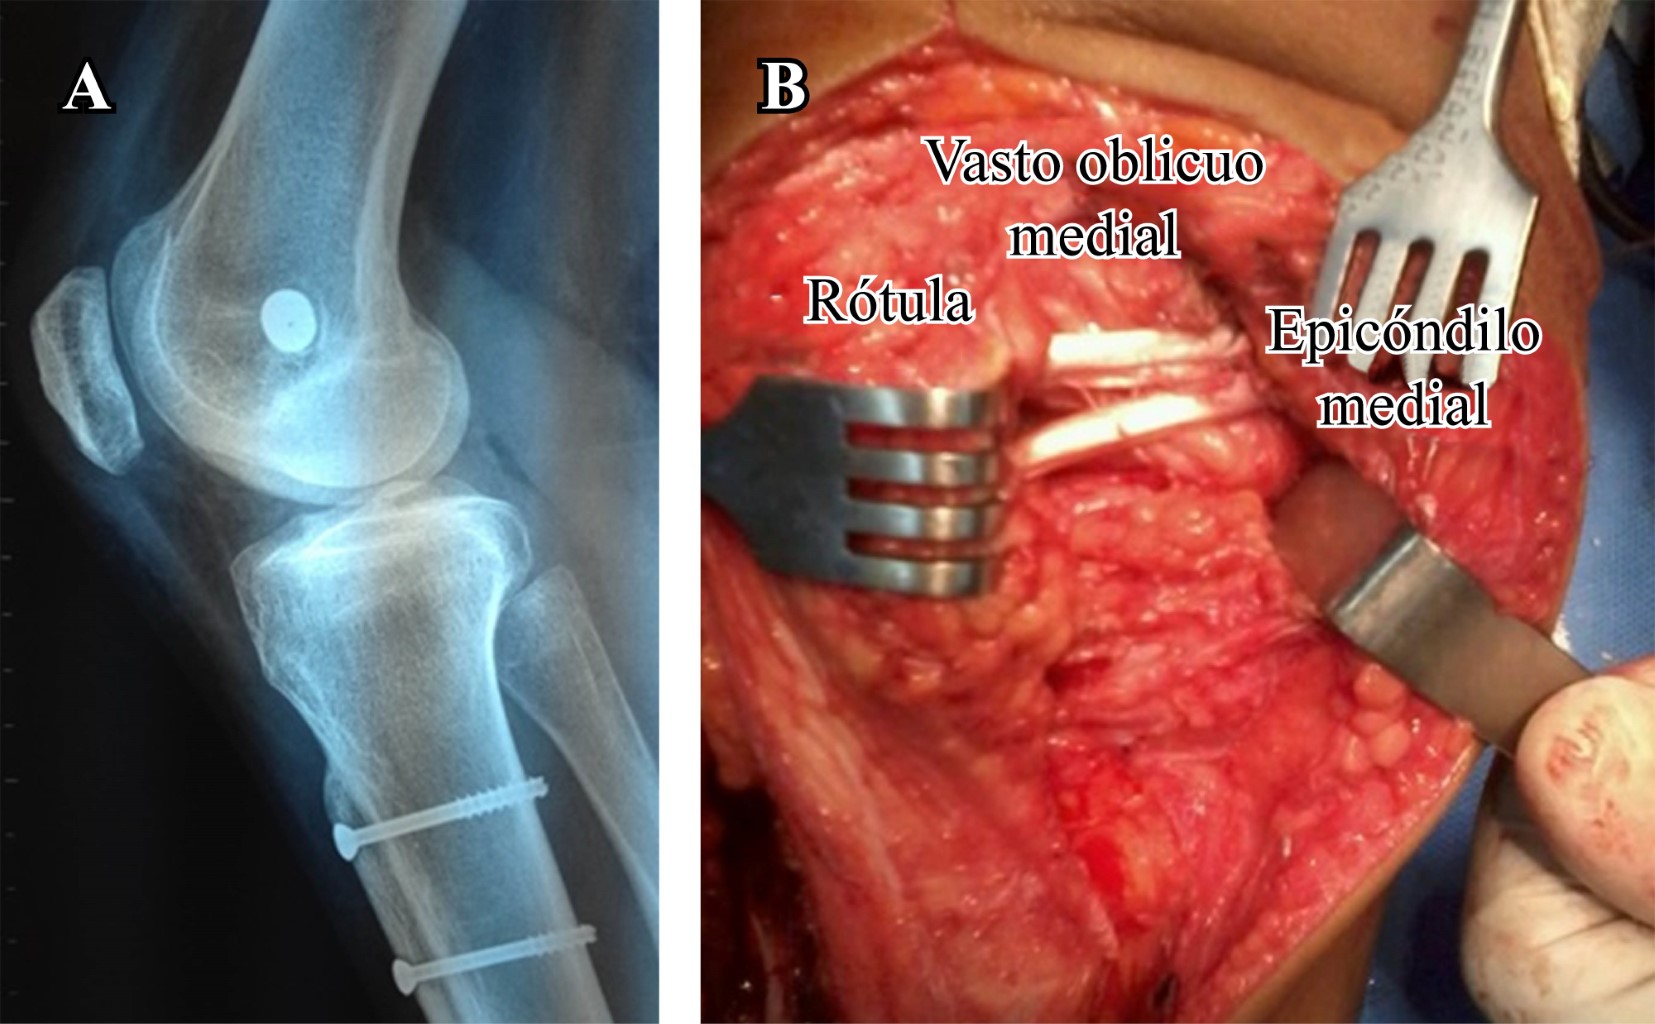

La transposición latero-medial pura de la tuberosidad tibial está indicada para distancias aumentadas del TT-TG mayor de 15-20 mm en ausencia de patela alta. Se estabiliza dicha transposición con dos tornillos de 4.5 mm de diámetro (a una distancia de 20 mm entre ellos) y se sutura el periostio lateral al fragmento de hueso previamente osteotomizado (Figura 3).

El procedimiento es completado con una reconstrucción del ligamento patelofemoral medial utilizando un injerto de tendón semitendinoso, el cual se tuneliza a través de la rótula y se fija en el punto de isometría femoral según Schottle (Figura 6).15

Realizamos una incisión recta longitudinal en la piel en la cara anterior de la rodilla desde el margen superior de la rótula hasta la articulación femorotibial mientras la rodilla se encuentra en 90o de flexión. Luego, la rodilla se coloca en extensión y se realiza una artrotomía siguiendo las fibras del vasto oblicuo medial, exponiendo 1-2 cm el borde medial de la rótula.

La rótula es evertida para la inspección de posibles lesiones osteocondrales tanto femorales como rotulianas y luego se retrae lateralmente, exponiendo y reconociendo el morfotipo troclear a tratar. Teniendo como objetivo principal disminuir la prominencia troclear y crear un nuevo surco de profundidad y vertientes anatómicos, se realiza la trocleoplastía planificada (Figuras 7 y 8). El procedimiento es completado con una reconstrucción del ligamento patelofemoral medial utilizando un injerto de tendón semitendinoso, el cual se tuneliza a través de la rótula y se fija en el punto de isometría femoral con un tornillo de interferencia.